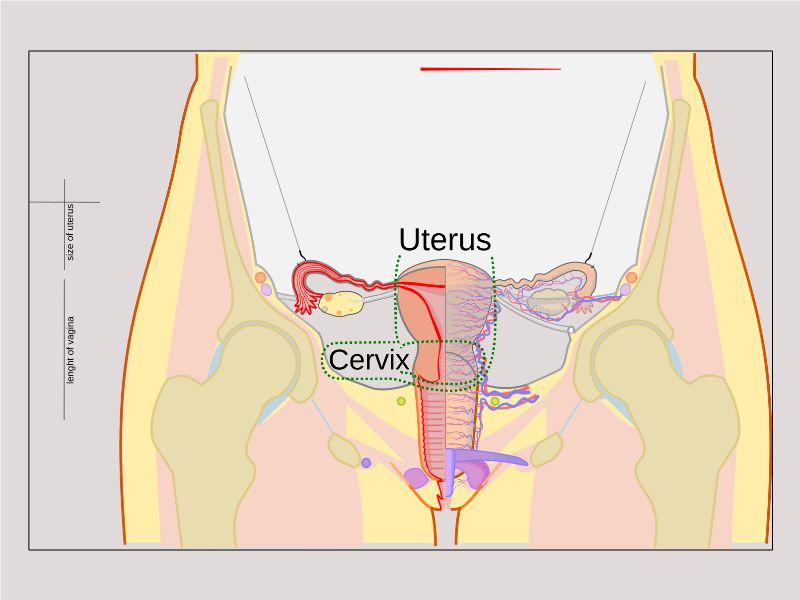

Uterus

Uterus

3 regions3 layers

Three regions

FundusBody

Cervix

Cervix

- Uterus projecting into vagina